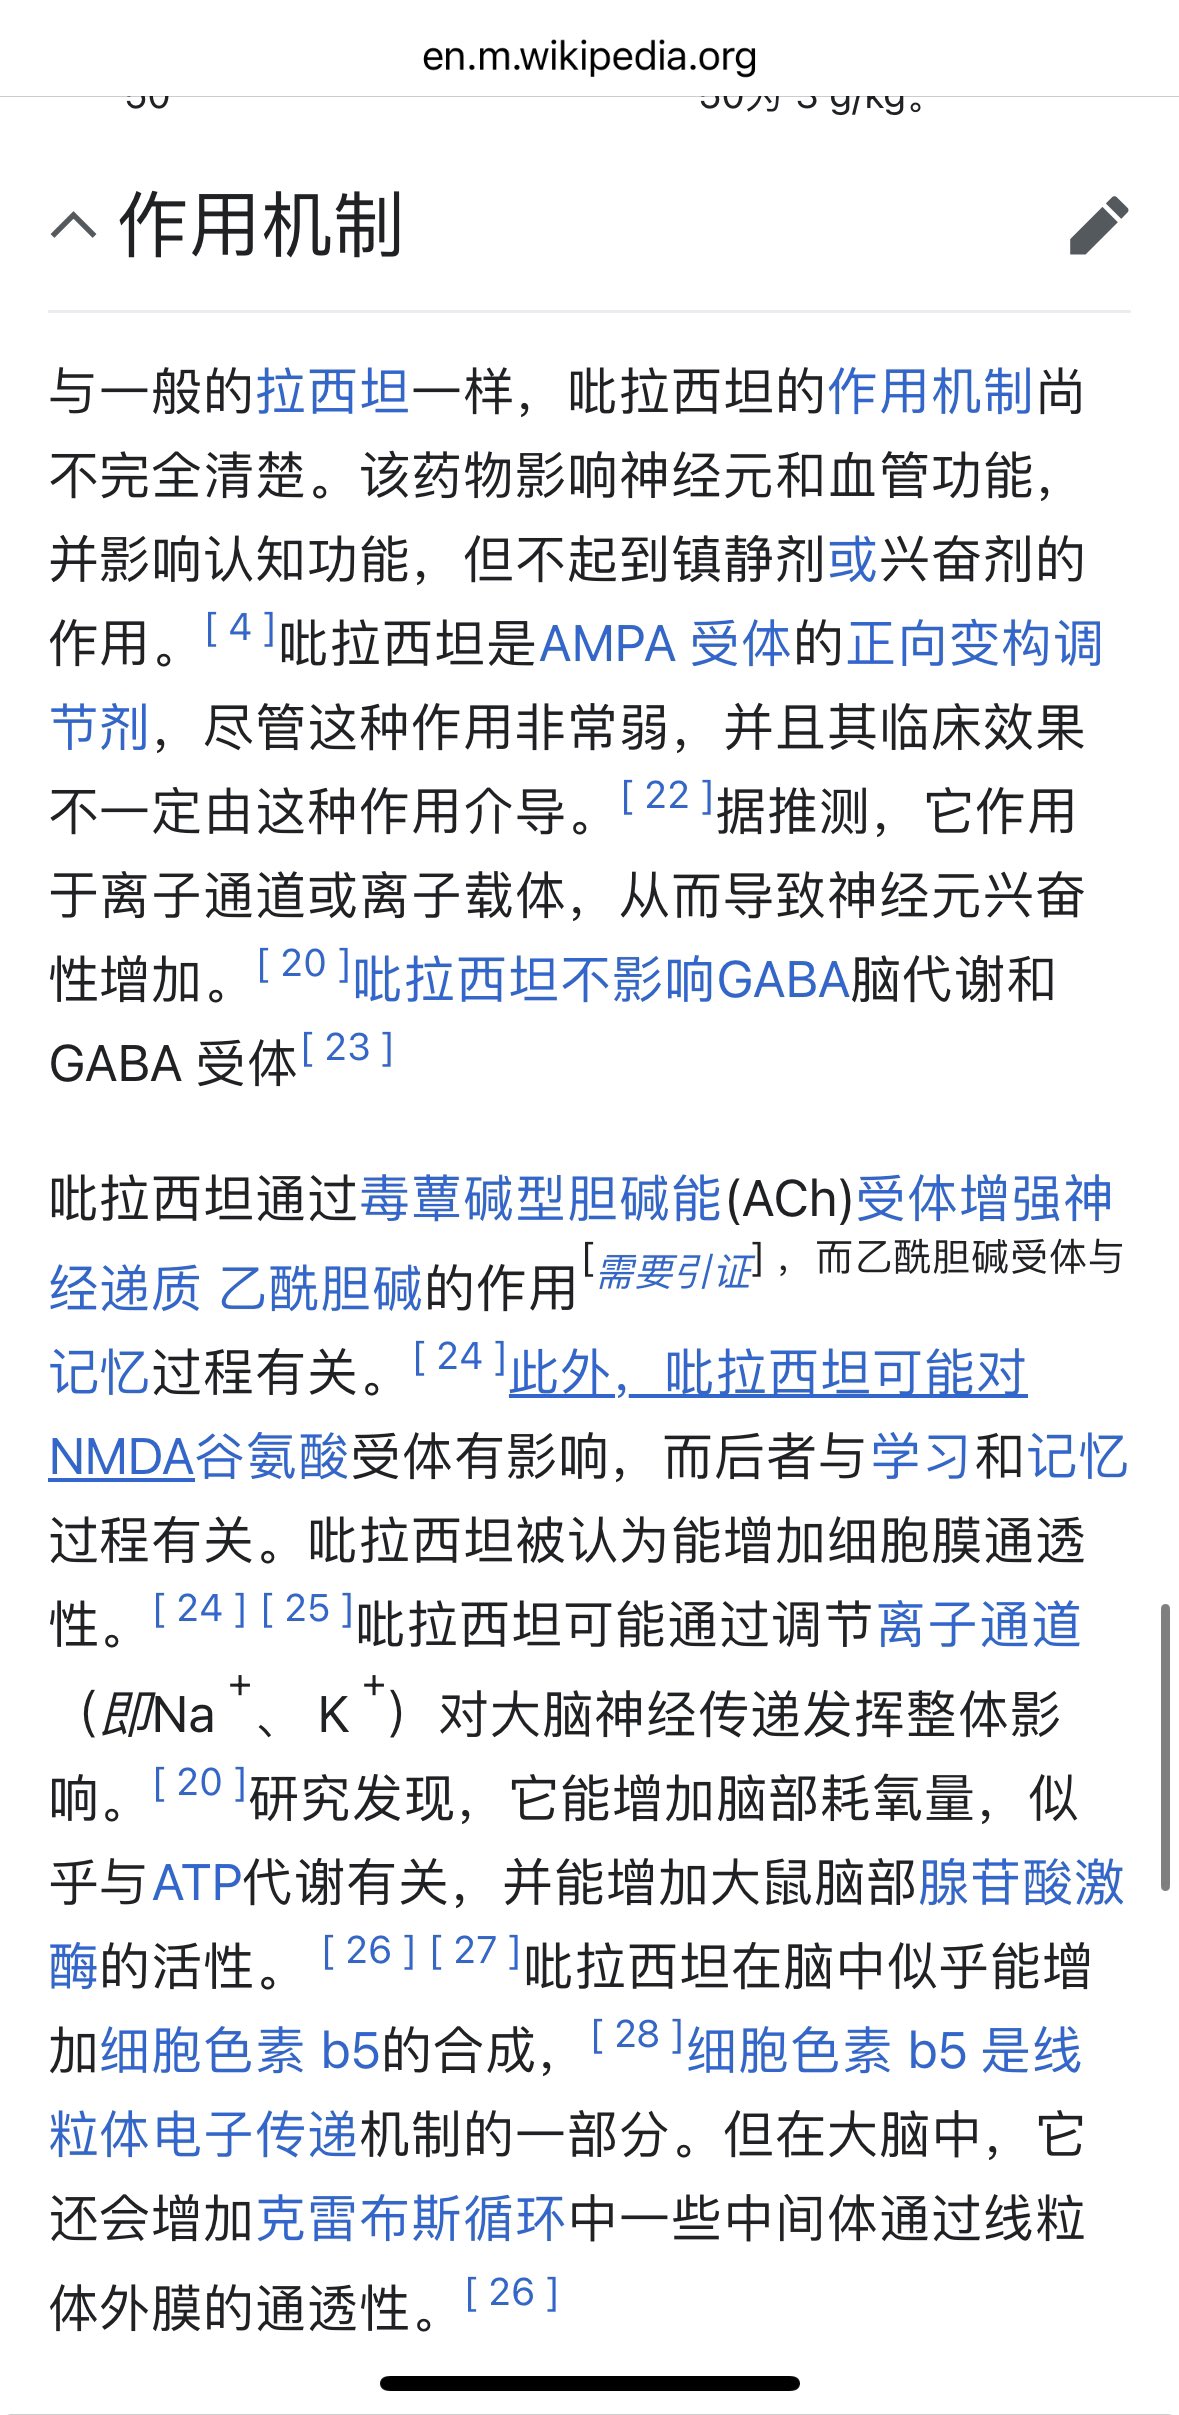

首先,从定义上讲,“反解离(anti-dissociative)”并不是一个标准的医学术语或者广泛认同的药理学分类。在正规资料,比如医学文献、维基百科、精神药理学教科书中,目前并没有“反解离药物”这个正式概念。

看上去像是为了描述某类特定效应而创造的术语(可能是nmda受体活性增强),用来对抗因NMDA受体拮抗剂(比如氯胺酮、DXM、PCP等)引发的解离体验(dissociation)。

那么更常见的是将其归入认知增强剂(cognitive enhancers),特别是改善认知连接性(connectivity)和现实感知(reality testing)的类型。

但其实在药理学上,单纯用“受体激动剂”来逆转“受体拮抗剂”的效应,有时会导致过度激活。

对于NMDA受体而言,过强的NMDA活化本身就与兴奋性毒性(excitotoxicity)和精神病样症状(psychotomimetic effects)有关,比如谷氨酸风暴可以引发严重的焦虑、妄想、乃至癫痫。

也就是说,简单地“激动-解除拮抗”在中枢神经系统是很危险的做法,尤其是对于易感个体(如有精神分裂素质的人)。

科学的处理方式一般是通过更细致的调节,比如微调NMDA/AMPA平衡、调节其他辅助途径(如GABA、5-HT、mGluR受体),而不是简单粗暴地用“NMDA增强剂”去顶回去。

而临床处理药物中毒中,其实医生更常用的做法是保守、支持性的治疗,比如补液,促进代谢,必要时镇静,以及监测生命体征防治并发症。

药物拮抗与受体激动之间,往往牵扯到的是复杂的适应性变化(receptor upregulation/downregulation),

不是简单的“给多一点刺激就能抵消”的关系